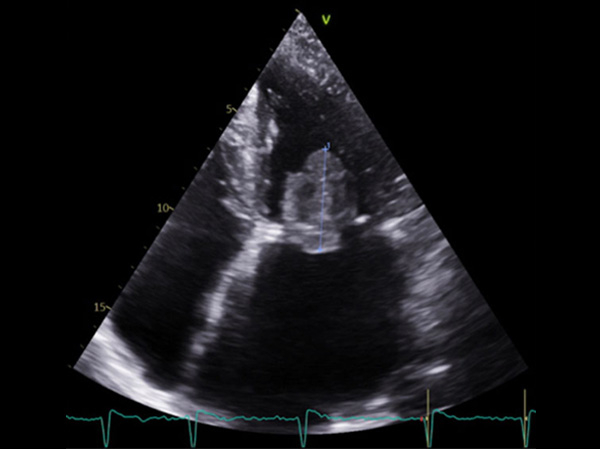

- Échocardiogramme transthoracique : volumineux thrombus de 40 mm de diamètre au toit de l’OG

Vidéos 5 à 7 et figure 9 : Masse arrondie de 43 mm de diamètre flottant librement dans l’oreillette gauche avec enclavement périodique dans l’orifice mitral : « ball thrombus »

Figure 8

Figure 9 : ball thrombus